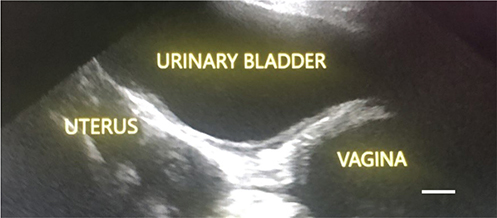

Transabdominal ultrasonography (more sensitive than radiography)54 is used to assess uterine wall thickness, identify retained fetal membranes, fetal tissues and to quantitatively measure uterine contents and echogenicity of those contents (Figure 3). A diseased uterus can be difficult to distinguish from a normal involuting uterus with minimal intraluminal fluid; however, serial measurements can be used to assess uterine contents and response to treatment.54 Radiography is used to diagnose retained fetuses.

Figure 3.

Figure 3. Transabdominal ultrasonographic image of a 5-year bully dog with severe lordosis and clinical signs of metritis; scale bar equals 1 cm